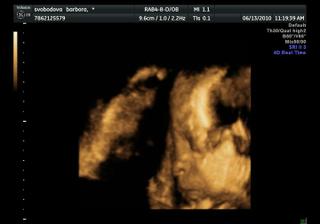

Náše bábetko a pupík🙂

Po 4 a půl letech jsme se rozhodli, že je nejvyšší čas pořídit si ten nejkrásnější dáreček 🙂 Po dvou snaženíčkách na nás vykoukly vytoužené //.